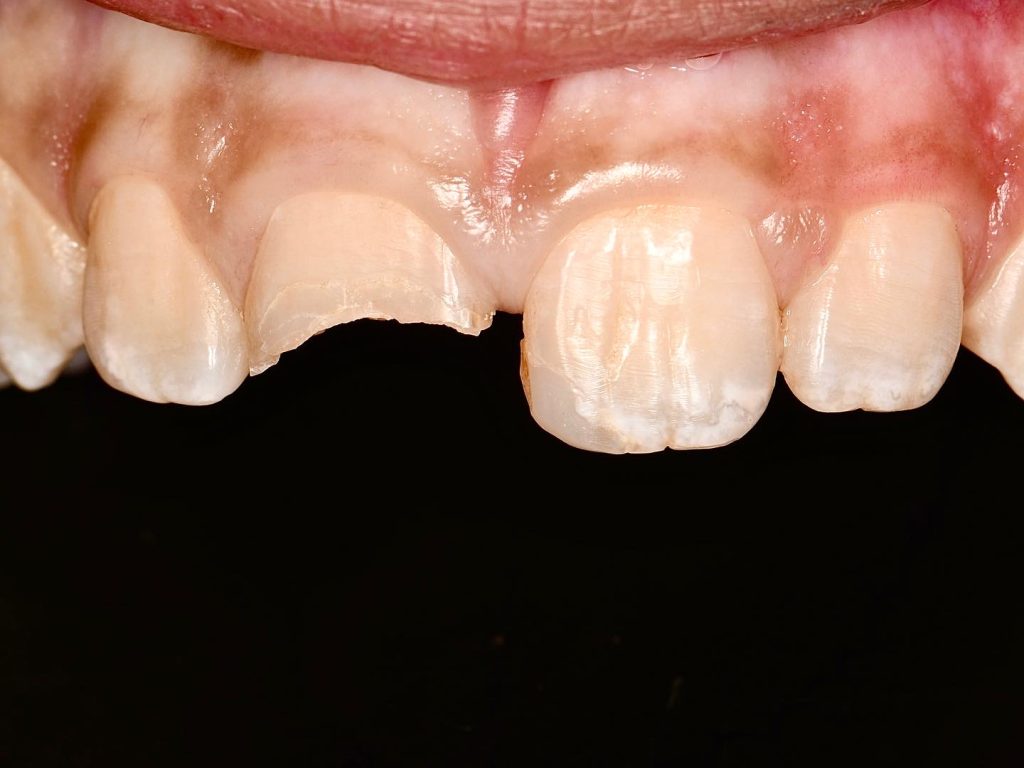

so we treated this incisor with direct composite restoration.

rubber dam isolation, ribbond used to support the remaining tooth , palatal shell built with free hand and layering composite was done

Se clearfil bond was used.

finishing and polishing in the same visit